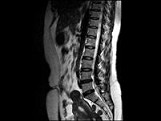

- 单项选择题女,37岁, 下腹部不适,MRI检查如图所示, 下列说法错误的是 ( )

A、子宫底部局部隆起,该病灶边界清晰

B、病灶T

WI信号与子宫肌层的信号相同C、病灶T

WI信号为明显低信号D、此为子宫粘膜下肌瘤

E、此为子宫浆膜下肌瘤